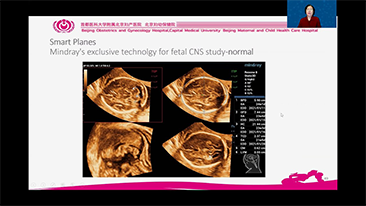

Com a plataforma ZST+ avan?ada, as solu??es inteligentes full-stack do Nuewa s?o projetadas especialmente para melhorar a saû¤de da mulher durante toda a gesta??o, desde o perûÙodo que antecede ao que procede û gravidez e û recupera??o pû°s-parto, a fim de oferecer diagnû°sticos abrangentes e eficientes para atender aos desafios clûÙnicos cada vez mais exigentes.